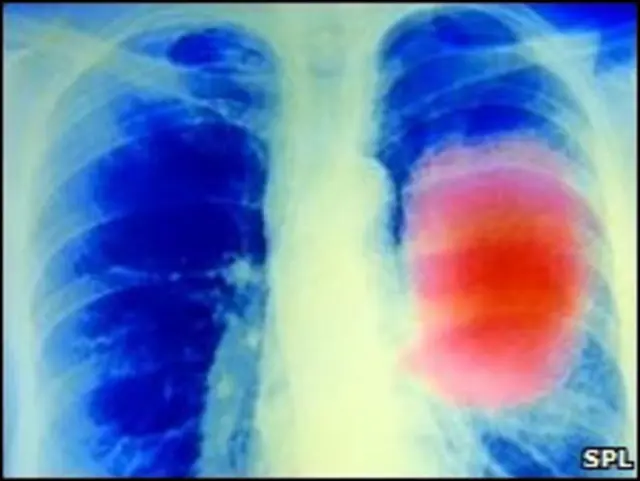

Di Inggris, kanker paru merupakan jenis kanker paling umum kedua dan sangat terkait dengan kebiasaan merokok.